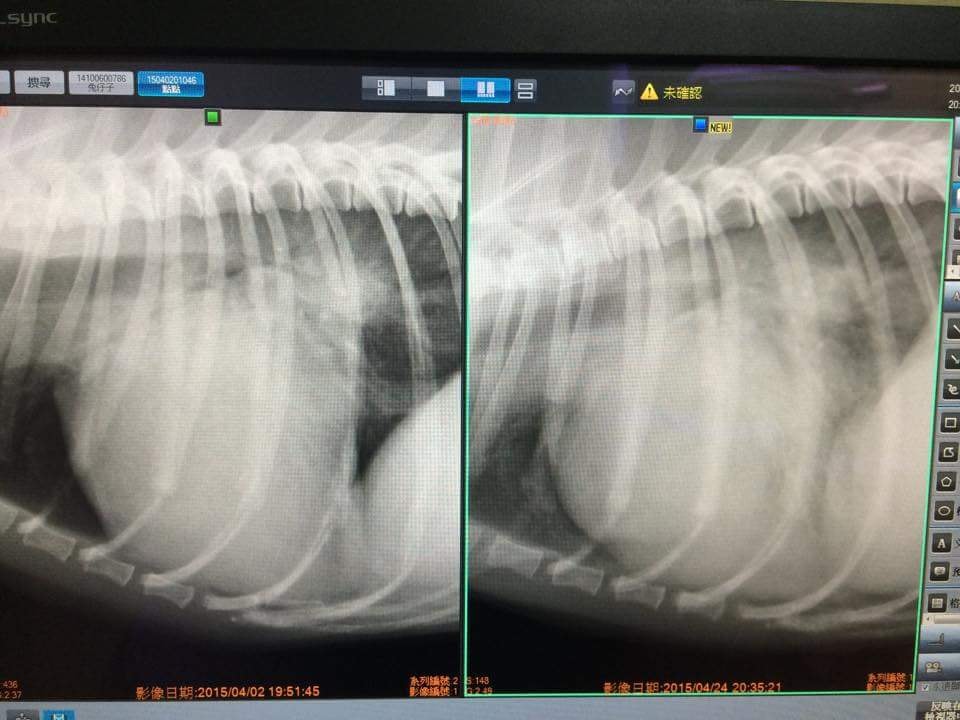

醫師經過抽血、X-RAY、心超等檢查後簡訊告知,排除是調藥後引起的藥物不適,是”急性肺水腫”!

照片是醫院傳來跟Sunny檢視病情的畫面,左邊是第一次去就診的肺部照;右邊是今天的肺部照

還拍了心臟超音波的畫面-心房與心室的缺口變大了….(好消息是腱索沒斷,壞消息是缺口變大…?!)